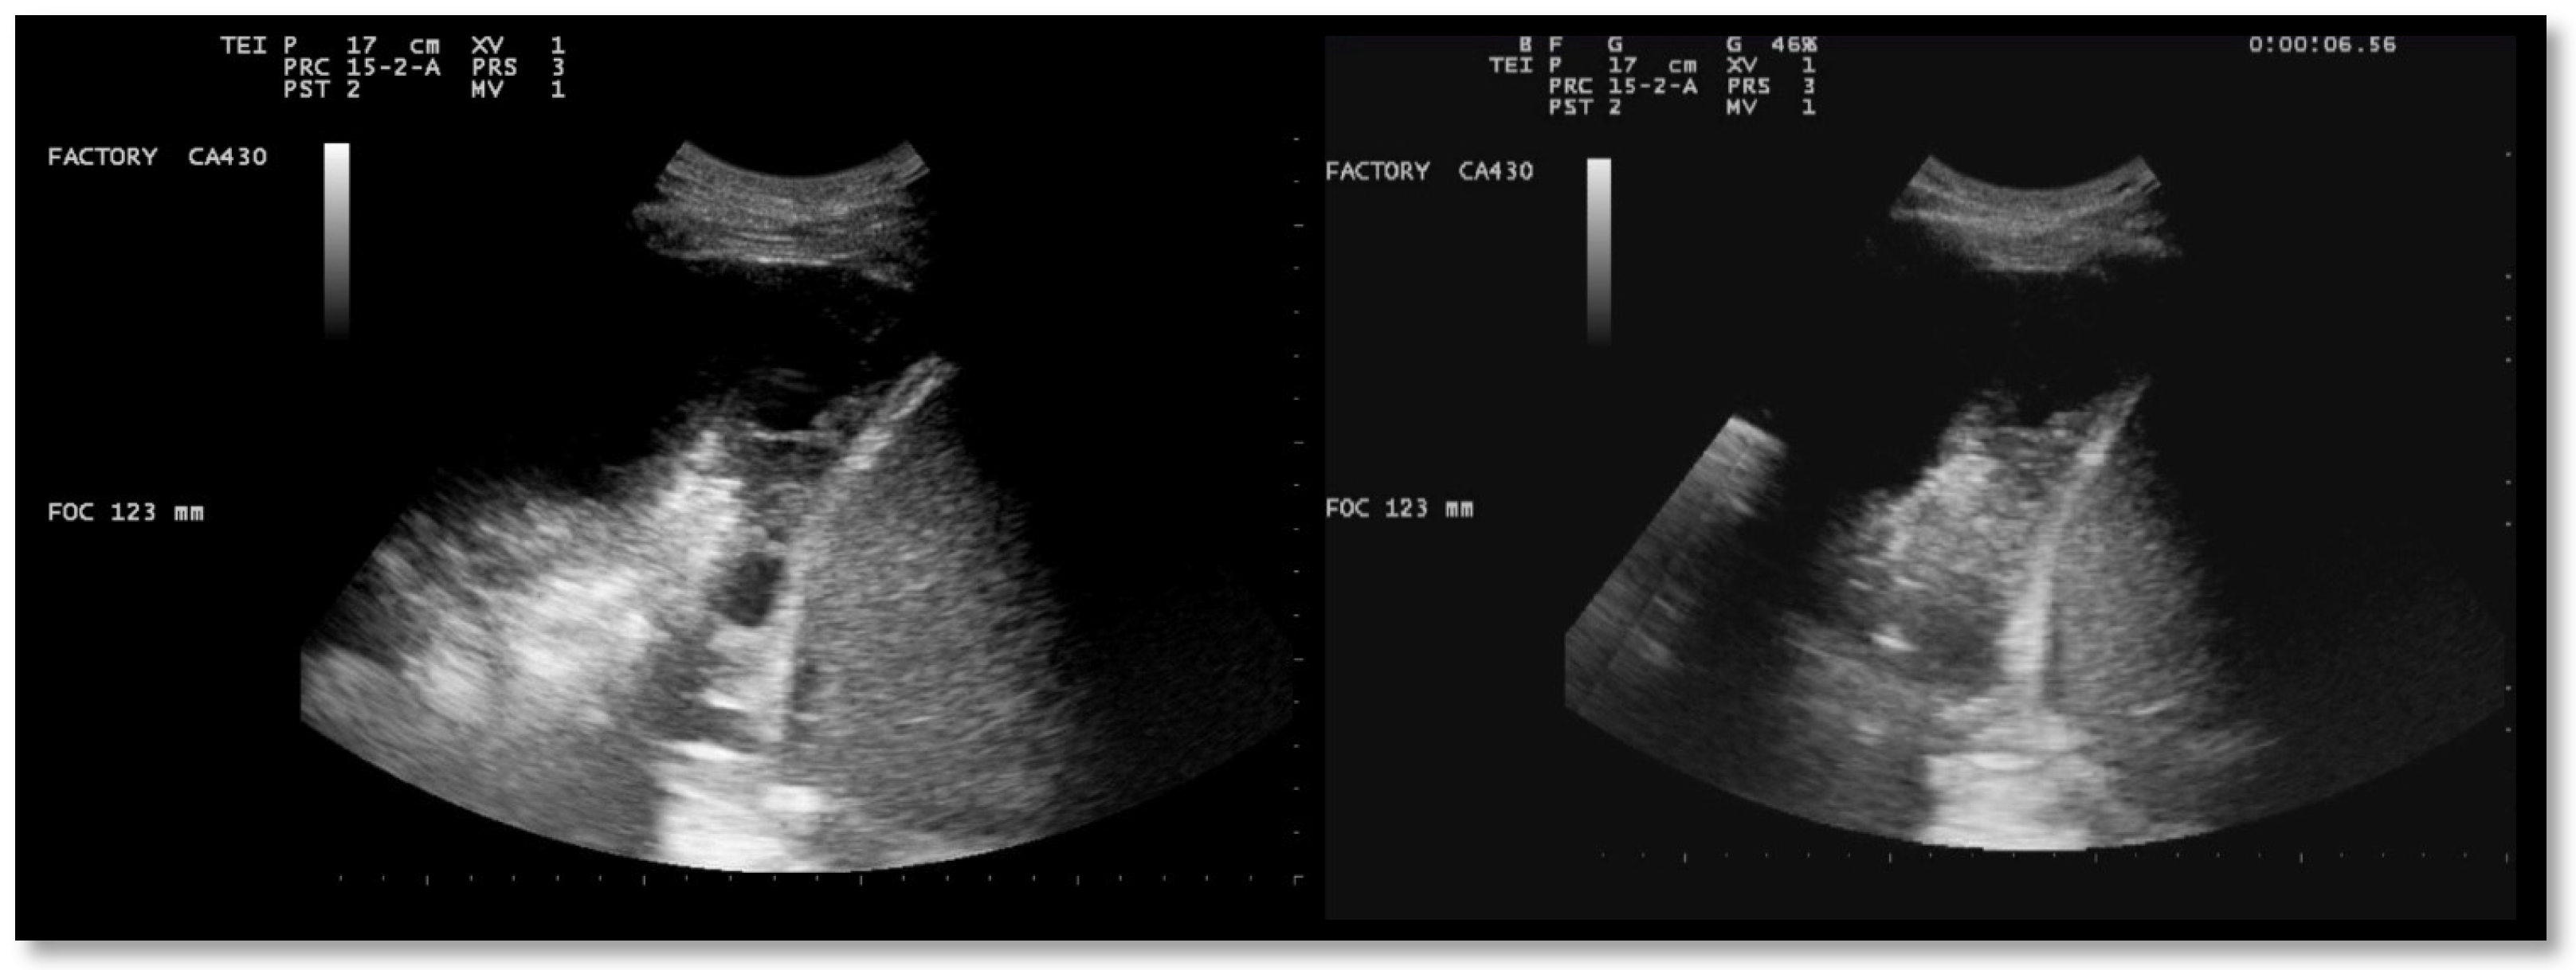

A chest US showed multiloculated PEff with septations of different thicknesses (Figure 9). A 12 Fr chest tube was placed, and 1000 mL of turbid fluid were drained. Samples were collected for microbiological and physicochemical analysis. Irrigation of the pleural cavity with 200,000 IU of urokinase in 50 mL of saline solution was performed under US guidance (Video 1). This was followed by the closure of the chest drain for 3 h, and then it was reopened. Further irrigation with 100,000 IU was performed 24 h later. Empiric antibiotic therapy with 500 mg azithromycin (q24h) for 6 days and 4.5 g piperacillin/tazobactam (q8h) for 2 weeks was administered. A chemical analysis of the pleural fluid revealed exudate. The microbiological study was negative.

Ultrasound observations 48 h after the administration of the first dose of urokinase showed the absence of fibrinous septa and a significant decrease in PEff (Figure 10 and Figure 11).

Figure 9. Chest ultrasound at admission showing multiloculated pleural effusion.

Figure 10. Chest US 48 h after urokinase. Minimum pleural effusion with residual fibrinous material and signs of lung re-expansion.

Figure 11. Chest US 48 h after urokinase. Chest tube in pleural cavity with residual pleural effusion.